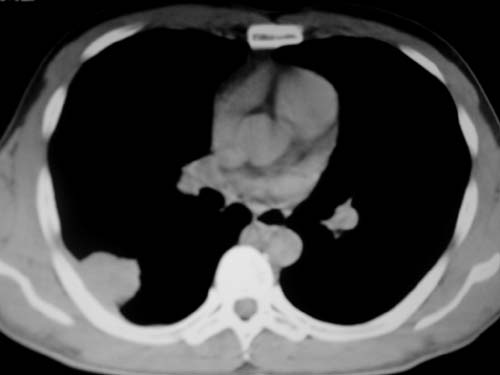

标题: CT19540: 31岁。自述结核性胸水治疗两个月后,在外院拍x线发 [打印本页]

标题: CT19540: 31岁。自述结核性胸水治疗两个月后,在外院拍x线发

右侧胸壁结节状软组织影伴相应肺叶内受侵,伴右侧胸腔积液。考虑:结核性可能大。

1、炎性包块;2、右侧少量胸膜积液。

1、炎性病变,结核可能;2、右侧少量胸膜积液。

右侧胸壁结节状软组织影伴相应肺叶内受侵,伴右侧胸腔积液,结合临床,首先考虑结核。

考虑结核性胸膜炎,胸膜肥厚,不除外胸膜间皮瘤可能,建议复查。

1)考虑右侧结核性胸膜结节。2)右侧胸膜增厚+包裹性胸腔积液。

结核性脓胸、肺内结核?